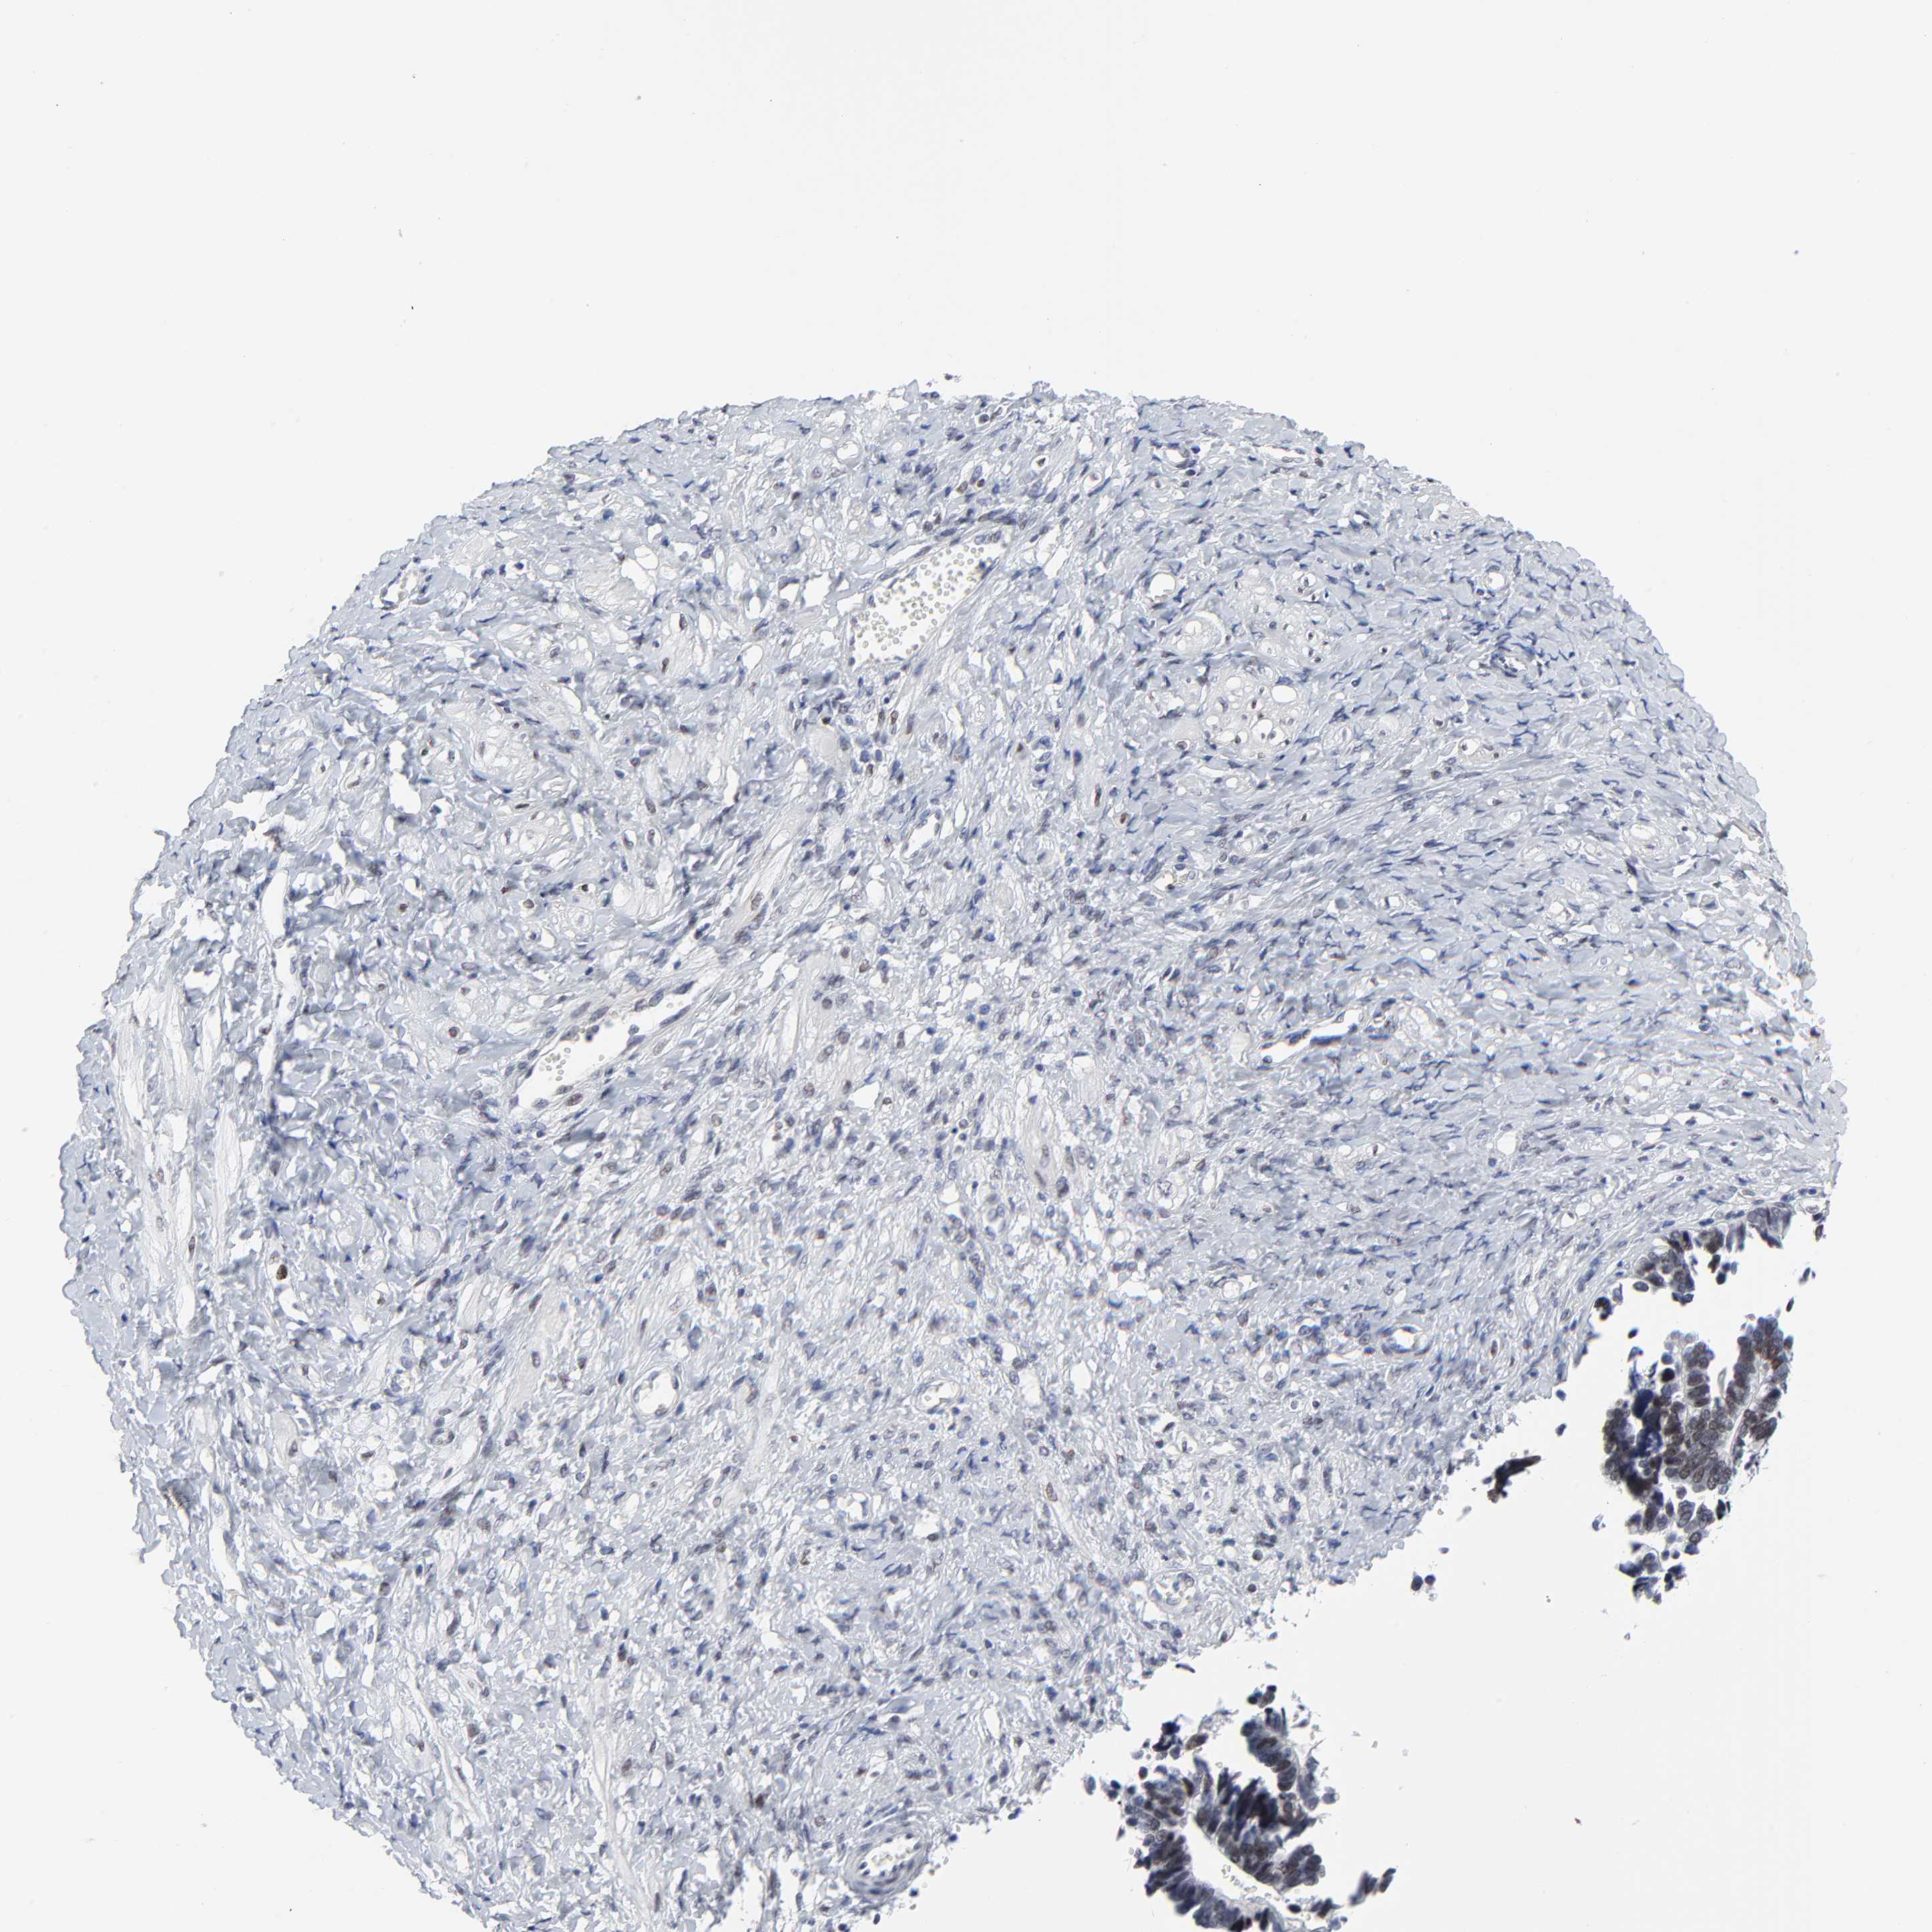

OVARIAN CANCER - Protein expressioni

A mouse-over function shows sample information and annotation data. Click on an image to view it in a full screen mode. Samples can be filtered based on level of antibody staining by selecting one or several of the following categories: high, medium, low and not detected. The assay and annotation is described here.

Note that samples used for immunohistochemistry by the Human Protein Atlas do not correspond to samples in the TCGA dataset.

Antibody stainingi

Antibody staining in the annotated cell types in the current human tissue is reported as not detected, low, medium, or high, based on conventional immunohistochemistry profiling in selected tissues. This score is based on the combination of the staining intensity and fraction of stained cells.

Each image is clickable and will lead to virtual microscopy that enables deeper exploration of all samples and also displays staining intensity scores, fraction scores and subcellular localization as well as patient and tissue information for each sample.

Antibody HPA003145

Staining

High

Medium

Low

Not detected

Intensity

Strong

Moderate

Weak

Negative

Quantity

>75%

75%-25%

<25%

None

Location

Nuclear

Cytoplasmic/membranous

Cytoplasmic/membranous,nuclear

Carcinoma, endometroid

Cystadenocarcinoma, serous, NOS

Cystadenocarcinoma, mucinous, NOS